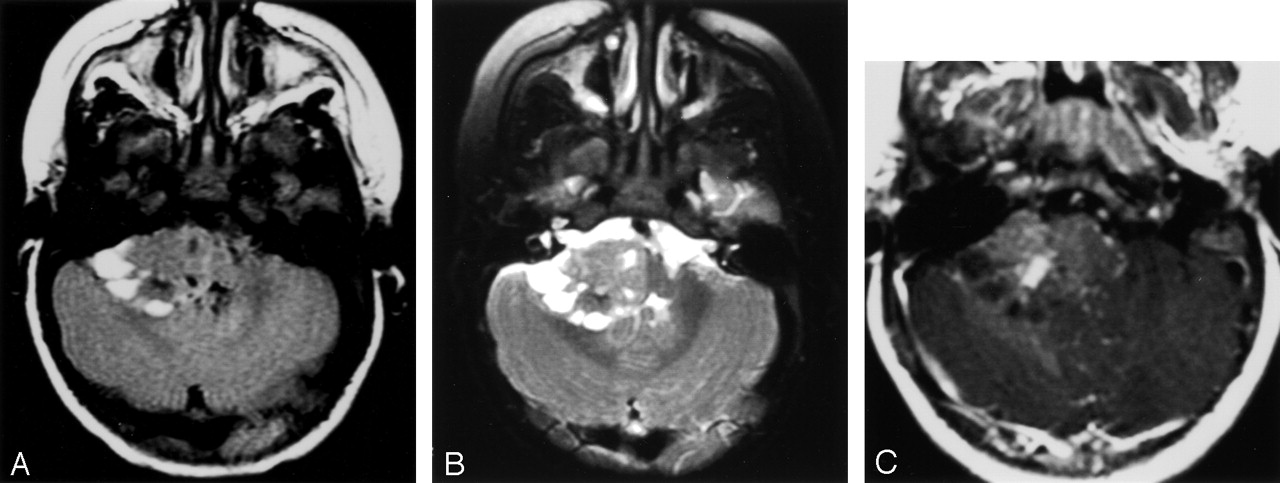

Cerebellopontile angle mass.

A, Fluid-attenuated inversion recovery image shows a right cerebellopontile angle extra-axial mass with solid and peripheral cystic components. Focal hypointensities correspond to calcifications shown on CT scans (not shown).

B, T2-weighted fast spin-echo image shows a right cerebellopontile angle extra-axial mass with solid and peripheral cystic components. Focal hypointensities correspond to calcifications shown on CT scans (not shown).

C, Contrast-enhanced image shows mild enhancement with a small, relatively more enhancing nodule.

All tumors showed marked heterogeneity on both CT scans and MR images. Readily visible multiple foci of calcifications measuring approximately 1 to 5 mm were present on the CT scans of all patients. No calcification >1 cm was seen. All the tumors had cystic and solid areas. The location of the cysts was remarkable in that in three patients, they were situated eccentrically between the solid portion of the tumor and adjacent brain (Figs 2–4). In one patient with a hemispheric mass, the cystic part was in the center of the tumor. The cysts showed increased attenuation on CT scans and increased T1 signal intensity on MR images, as compared with the CSF. The walls of the eccentric cysts showed varying degrees of enhancement. The solid component of the masses was heterogeneous and showed varying degrees of increased signal intensity on T2-weighted images, decreased signal intensity on T1-weighted images, and mildly increased attenuation on CT scans. Even within the solid portion of the masses, there were small cystic areas. Enhancement was variable: moderate to marked in two patients (thick, irregular, nodular rim enhancement) and mild in others.

Aggressive features of all tumors were shown by the imaging studies. Hydrocephalus, apparent invasion of the adjacent brain and dura, and marked mass effect were present in all patients. One of the hemispheric tumors grossly invaded the skull (Fig 1D). Despite this aggressive appearance, there was little, if any, edema in the surrounding parenchyma.